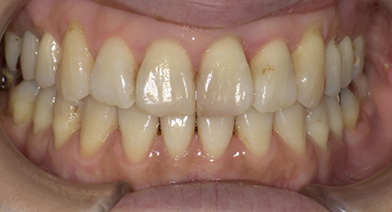

- 治療前治療後

-

上下顎前歯部叢生症例

- 主訴

- 八重歯、前歯の凸凹、上顎右側犬歯低位

- 診療名

- 13の低位、上下顎前歯部叢生、下顎正中右側偏位

- 年齢・性別

- 20代女性

- 治療期間

- 1年8ヵ月

- 治療費用

- 精密検査代:38,000円

装置代:840,000円

処置代:102,000円

保定装置代:40,000円

⇒総額:1,020,000円(税込み)

※治療当時の金額となります。

- 治療説明

- 上下顎大臼歯のアップライト、IPRによるスペースメイキング、17抜歯し、18を咬合させる

抜歯:17番(計1本)

治療装置:インビザライン

固定装置:なし

リテーナー:fixリテーナー+クリアリテーナー

- リスク・副作用

- 痛み・治療後の後戻り・歯根吸収・歯髄壊死・歯肉退縮

症例の詳細を見る